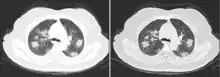

Imaging

Chest CT scans may be helpful to diagnose COVID‑19 in individuals with a high clinical suspicion of infection but are not recommended for routine screening.[167][179] Bilateral multilobar ground-glass opacities with a peripheral, asymmetric, and posterior distribution are common in early infection.[167][180] Subpleural dominance, crazy paving (lobular septal thickening with variable alveolar filling), and consolidation may appear as the disease progresses.[167][181] Characteristic imaging features on chest radiographs and computed tomography (CT) of people who are symptomatic include asymmetric peripheral ground-glass opacities without pleural effusions.[182]

Many groups have created COVID‑19 datasets that include imagery such as the Italian Radiological Society which has compiled an international online database of imaging findings for confirmed cases.[183] Due to overlap with other infections such as adenovirus, imaging without confirmation by rRT-PCR is of limited specificity in identifying COVID‑19.[182] A large study in China compared chest CT results to PCR and demonstrated that though imaging is less specific for the infection, it is faster and more sensitive.[166]